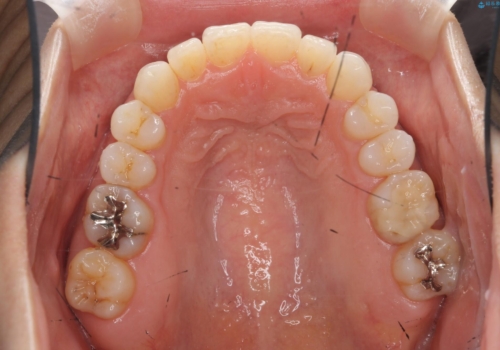

30代女性 前歯のがたつき

- 30代女性

- インビザライン

- 1年5ヶ月

- 前歯のがたつきを主訴に来院。

右下の奥の銀歯も治療しています。

- 115.5万円 矯正治療 85万円、奥歯ジルコニアクラウン11万円(ZrCr 10万円、仮歯1万円、矯正用仮歯2万円)セラミックインレー7万円費用は治療当時の料金となります

下の前歯を下げるため、IPR(歯をわずかに削る処置)を行っています。